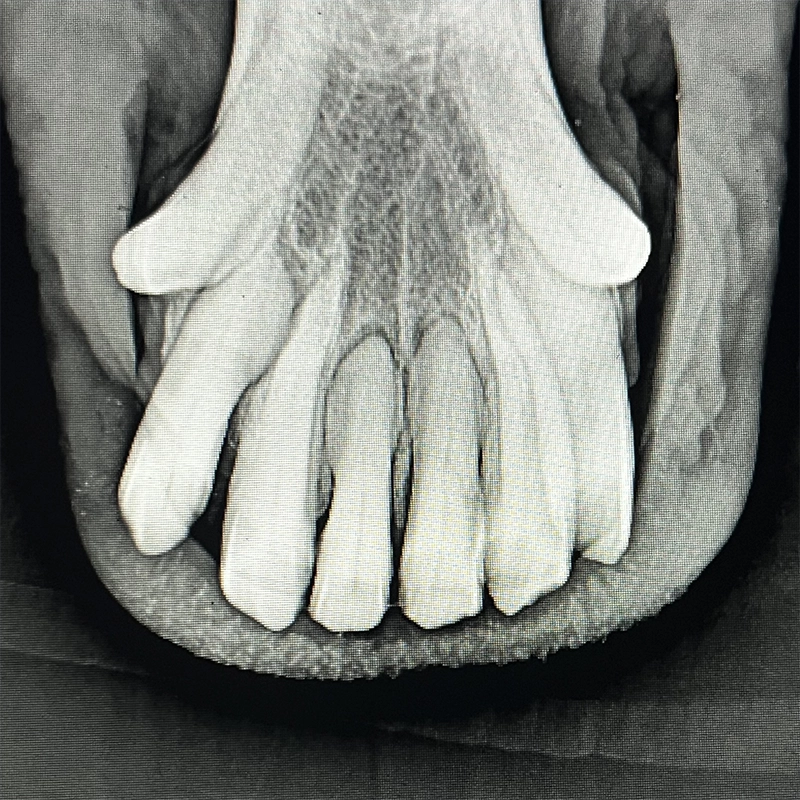

If the incisors are significantly damaged and conservative treatments no longer provide sufficient relief, extraction of the affected teeth is often the last option to permanently eliminate chronic pain and restore the horse’s quality of life.

Extraction is performed under controlled clinical conditions with appropriate sedation, targeted pain management, and proper regional anesthesia. A careful, tissue-preserving technique helps protect surrounding structures and supports uncomplicated healing.

Following healing, most horses show a marked improvement in comfort, eating behavior, and overall well-being. In many cases, quality of life and vitality improve significantly and sustainably.